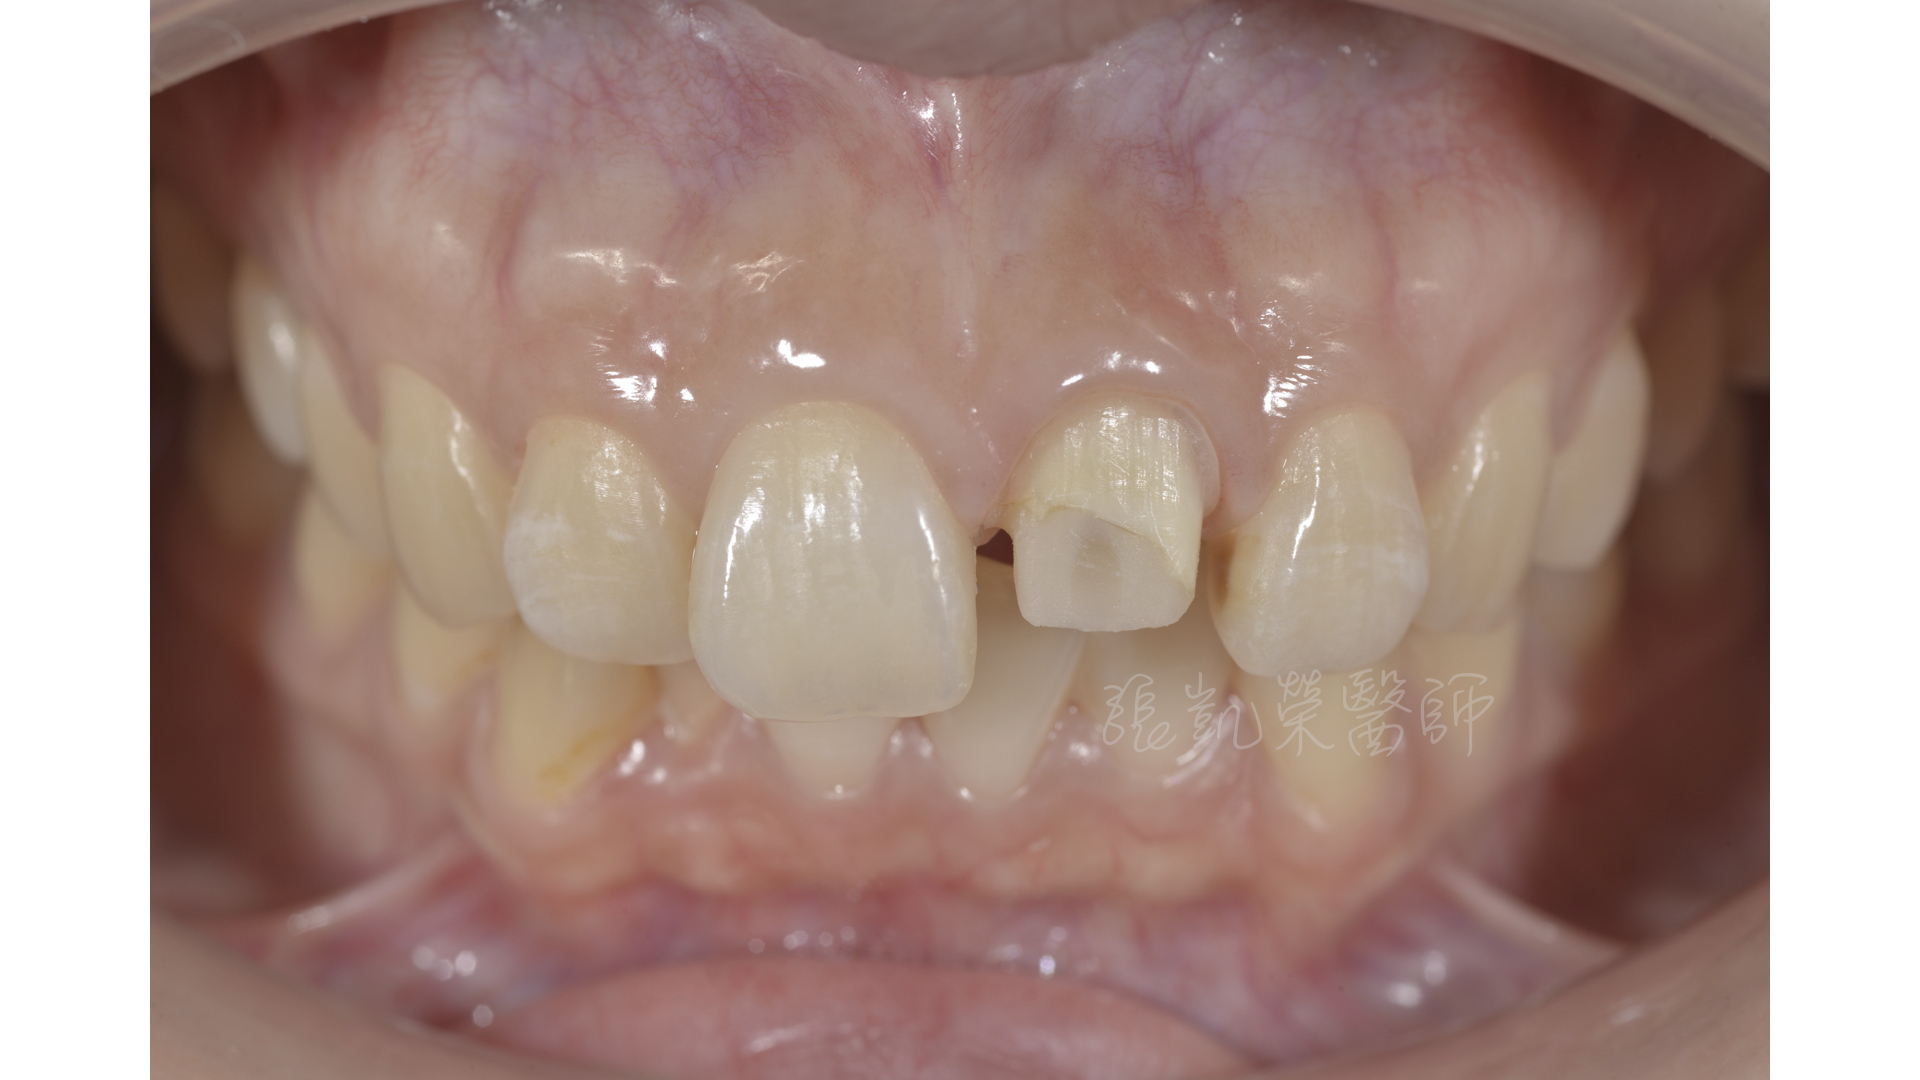

討論之後,榮醫師建議在全瓷冠治療之前,要先做齒內美白,把牙齒與牙根的顏色淡化,之後再藉由碳纖維柱釘與全瓷冠恢復牙齒的強度與美觀。